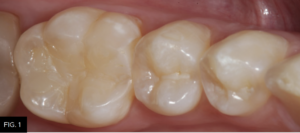

The patient shown in FIG. 1 presented with radiographic decay (FIG.2 and 3) on the distal surfaces of tooth numbers 19 (36) and 21 (34).